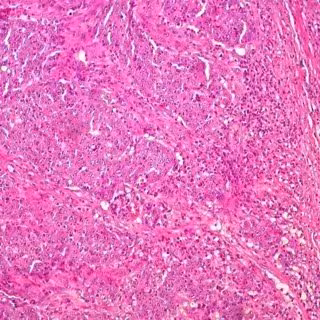

Cáncer de colon